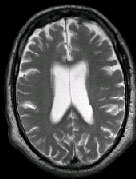

IMAGING FINDINGS: The CT was performed on AIC’s new 16-slice helical multi-slice CT (MSCT). Both routine single-slice and thin-section helical scans were obtained and 3D/Multiplanar images were performed on the Advanced 3D workstation. Fig. 1 shows an image at the level of the lateral ventricles with possible high density within the sulci on the right (arrow). To confirm this finding, an MRI with contrast was then obtained on AIC’s 1.5-Tesla high-field, short-bore Siemens MRI. Fig. 2a-b are T2-weighted images at the same level showing NO definite abnormality. T1-weighted images (not shown) were also negative. The post-contrast images (not shown) showed NO abnormal enhancement in this region, either. Diffusion-weighted images were also negative. However, Fig. 3a-b, which are FLAIR images, demonstrate clear hyperintensity within multiple sulci involving the right temporo-parietal area (arrows).

DIAGNOSIS: The FLAIR images are compatible with Subarachnoid disease. The Differential Diagnosis includes: (1) Subarachnoid Hemorrhage (SAH); (2) Meningitis; (3) Infarct; (4) Flow Artifact. Lack of enhancement is against meningitis. Acute infarct was ruled out on the basis of negative Diffusion MRI and lack of cytotoxic edema on the FLAIR images. Focal abnormality is against flow artifact (which is more diffuse and usually in the posterior fossa on FLAIR images). The clinical history of trauma and the high-density on CT and hyperintensity on FLAIR images within the sulci are diagnostic of Acute Post-traumatic Subarachnoid Hemorrhage (SAH).